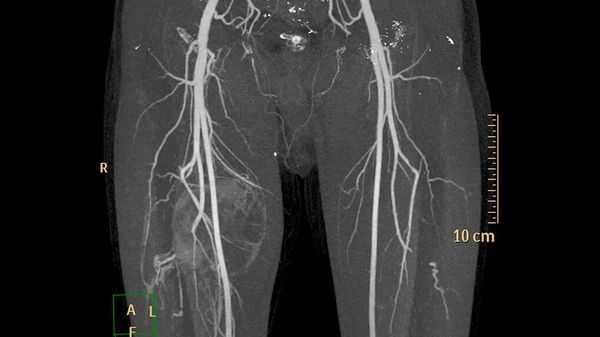

Дополнительные методы обследования для выявления поверхностных и локализованных поражений, как правило, не требуются. В случае же обширного распространения при первоначальной диагностике, для оценки костной ткани и при планировании лечения применяют методы визуализации:

- ультразвуковое исследование (УЗИ) и магнитно-резонансную томографию (МРТ) для первоначальной диагностики [12] ;

- компьютерную томографию (КТ) для оценки костной ткани;

- рентгеноконтрастную флебографию (введение в просвет вен рентгеноконтрастного вещества) для планирования лечения [7] .